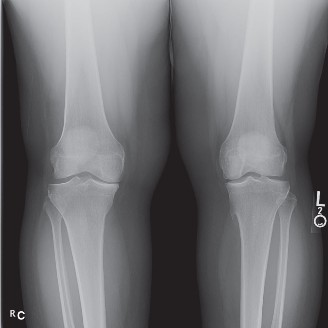

Standard radiographic evaluation of the knee is the first-line imaging modality for anterior knee pain. The patient's initial X-rays (Figures 9-1 A-C) include a weight-bearing anteroposterior (AP), a true lateral at 30 degrees of flexion, and an axial (Merchant or Sunrise) view.

The AP view demonstrates normal tibiofemoral joint spaces with no evidence of osteochondral lesions, loose bodies, or degenerative changes. The lateral view is scrutinized for patellar height. The Insall-Salvati ratio (the ratio of the patellar tendon length to the greatest diagonal length of the patella) is calculated at 1.05, which falls within the normal range (0.8 to 1.2), ruling out patella alta or baja. The lateral view also shows no evidence of trochlear dysplasia; the crossing sign is absent, and the trochlear bump is not prominent.

The Merchant view is arguably the most critical radiograph for this patient. It reveals a subtle lateral tilt of the patella and mild lateral subluxation. The sulcus angle measures 138 degrees (normal is typically <145 degrees), indicating adequate trochlear depth. However, the congruence angle is slightly lateralized, confirming the clinical suspicion of lateral patellar maltracking. There is no evidence of advanced patellofemoral osteoarthritis, osteophyte formation, or subchondral sclerosis.